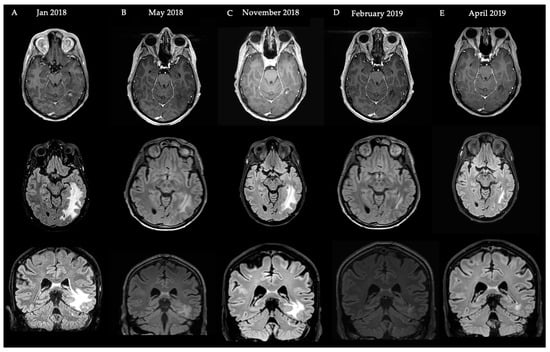

4.1. Case Illustration 1

4.2. Case Illustration 2